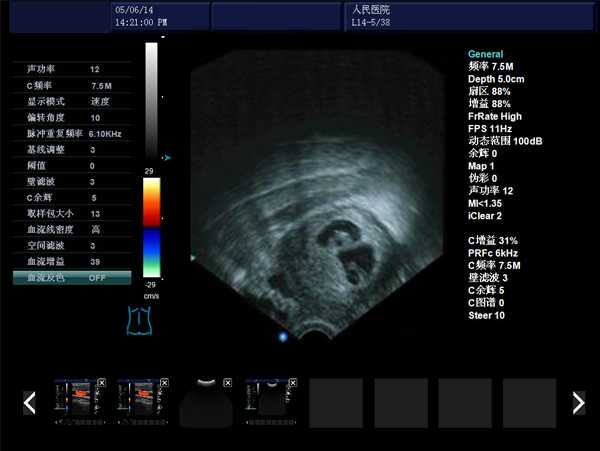

DW-480全數字超聲婦產科手術監視儀

DW-480

探頭與陰道窺器相結合,不進入宮腔,不占手術宮頸空間,手術更方便

實時動態高線密度超大角度掃描,有效提升橫向分辨力和側向分辨力、圖像自然更清晰

采用大容量電影回放,實時精微顯示等全數字圖像處理技術,宮腔內部圖像清晰可辨,不容錯過一點殘留,手術干凈徹底,避免了吸宮不全、漏吸等并發癥的發生